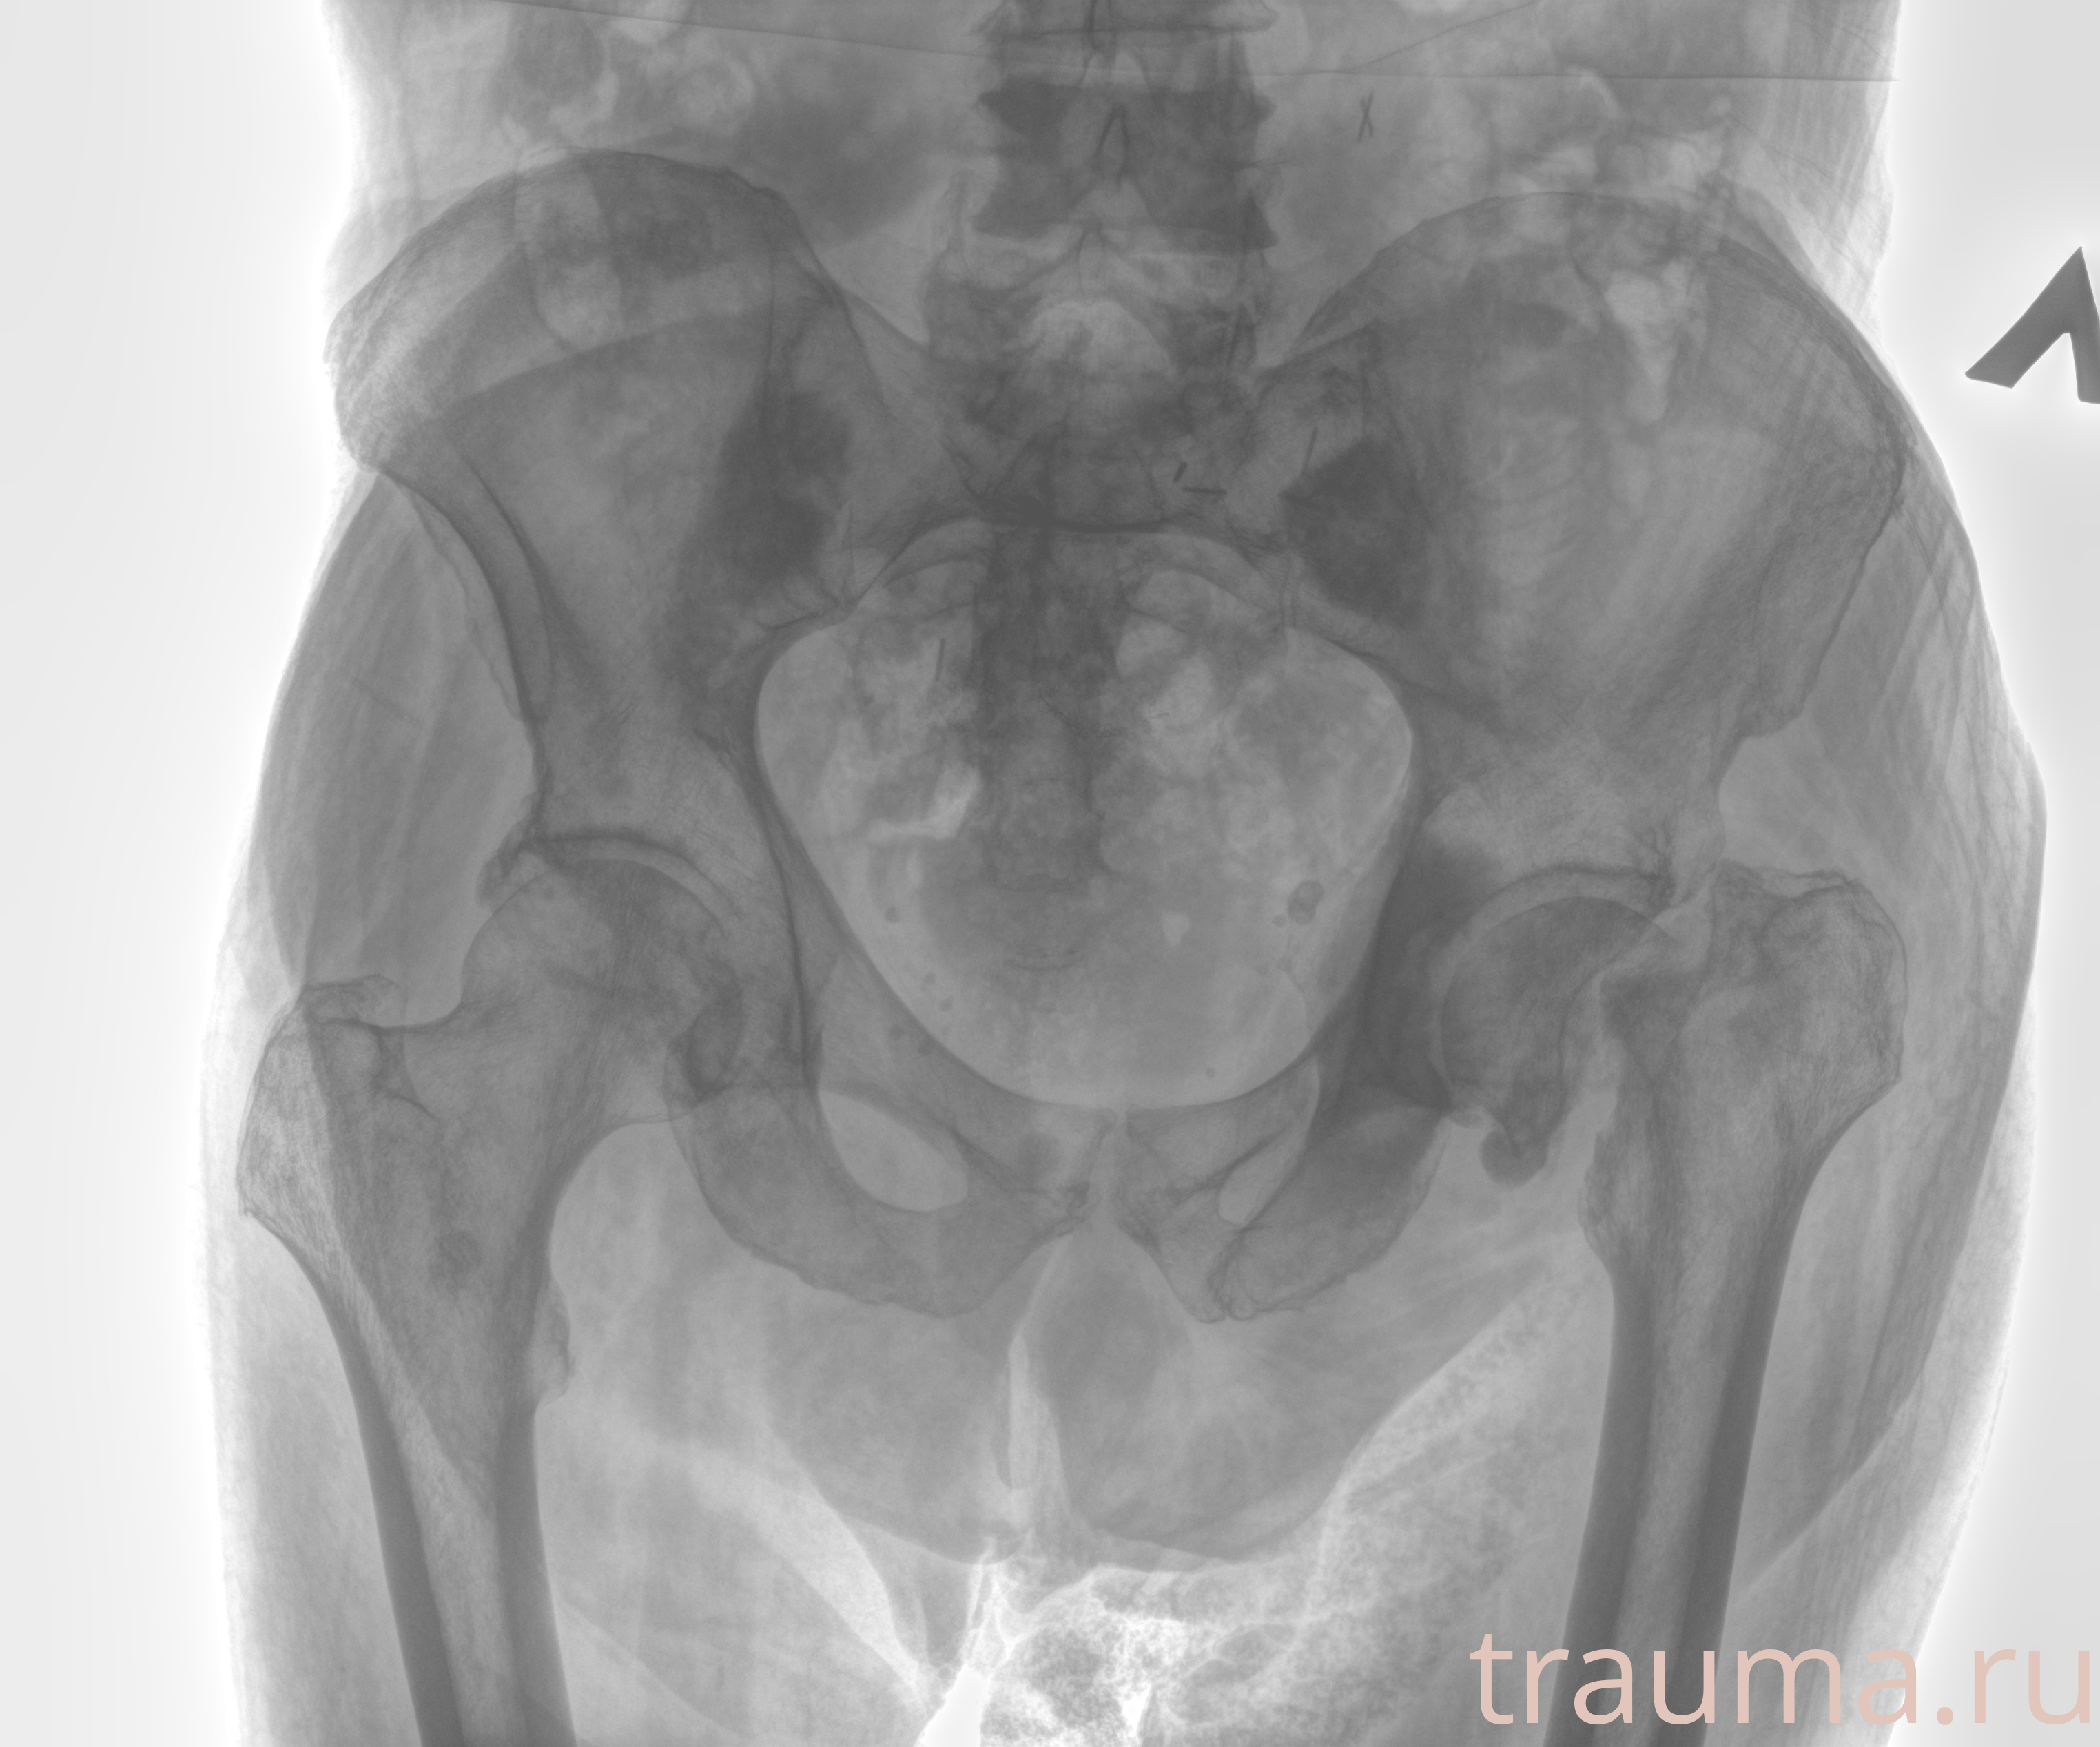

Рентгенограммы

Рентген на дому: по вашему адресу приезжает врач-рентгенолог, травматолог-ортопед с мобильным рентгеновским аппаратом, проводит диагностику травмы или заболевания, делает необходимые рентгенограммы, дает рекомендации по дальнейшему лечению. Получить качественные снимки в домашних условиях возможно благодаря уникальной методике, разработанной МосРентген Центром для института  Склифосовского